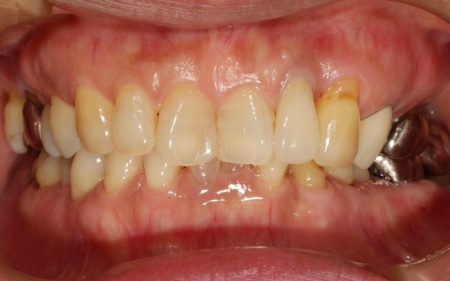

60代女性 変色した前歯に根管治療を施しセラミックの被せ物を装着した症例

拝見したところ、左上の前歯に変色が見られました。この歯は神経が死んでしまった失活歯です。

後日、完成したセラミックの被せ物を装着し、形や噛み合わせに問題がないかを確認して治療を終了しました。